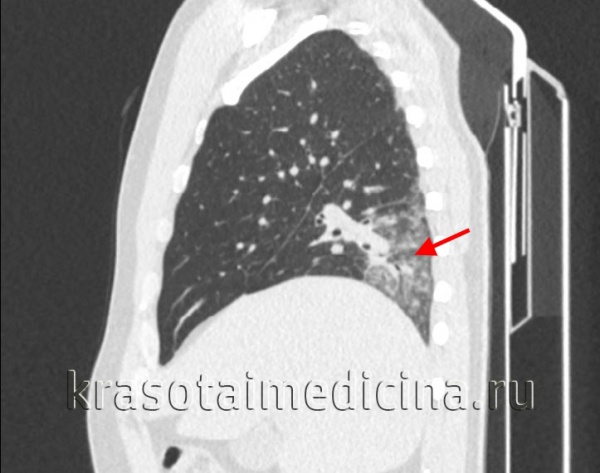

При подозрении на острую пневмонию назначается рентгенография легких в двух проекциях в динамике (на 7-10 день и 3-4 неделе). Рентгенологическим доказательством инфильтративных изменений при крупозной и крупноочаговой пневмонии является сегментарное или долевое гомогенное интенсивное затенение легочной ткани; при бронхопневмонии – неоднородное затенение части доли средней и малой интенсивности с захватом перибронхиальных и периваскулярных участков. В случае замедления рассасывания инфильтратов при острой пневмонии показана КТ легких.

КТ органов грудной клетки. Участок воспалительной инфильтрации (пневмония) в задних каудальных отделах нижней доли правого легкого